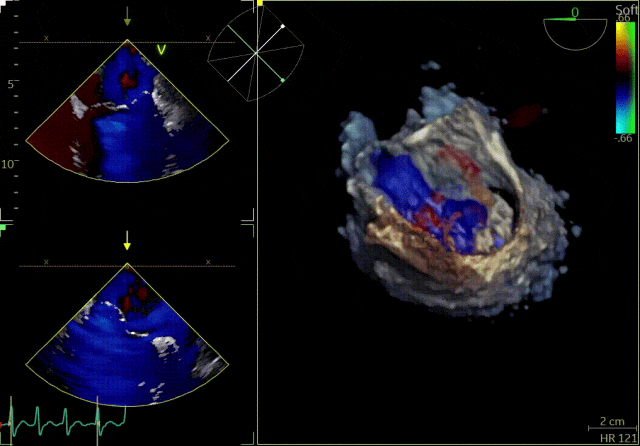

患者为41岁男性,心脏彩超提示:二尖瓣P2脱垂合并房性机制,左心扩大、瓣环扩张,反流主要来源于2区。反流宽度:20mm,2区瓣叶长度:2.2/1.3cm,AP径:43mm,瓣口面积:6.0cm²。

3D

3D彩色